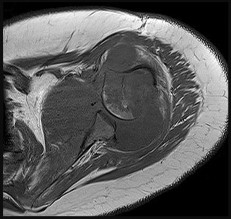

The lesion in the posterior intercondylar knee notch is a benign synovial hemangioma. Intralesional calcifications, classically associated with hemangiomas, are frequently not identified on plain radiographs. The MR imaging reveals a hypervascular lesion with multiple filling defects, with hyperintensity on T2-weighted images and low-to-intermediate signal intensity on T1-weighted images. Histologically, vascular lakes within fine capillaries with a synovium on the surface of the lesion are characteristic of this condition. Many patients with synovial hemangioma have pain, swelling, stiffness, or mechanical symptoms. The correlation of symptoms with the hemangioma for this patient is unclear because there was recent trauma and a concurrent meniscus tear. Simultaneous treatment of both potential sources of pain is typically recommended. As with PVNS, the disease can be localized or diffuse. Surgical excision, either open or arthroscopic, is the recommended treatment. PVNS is the most common intra-articular tumor, but hypointensity in either the diffuse or localized type is characteristic in both T1- and T2-weighted images. Synovial sarcoma, although often found close to a joint, is not characteristically found within a joint.